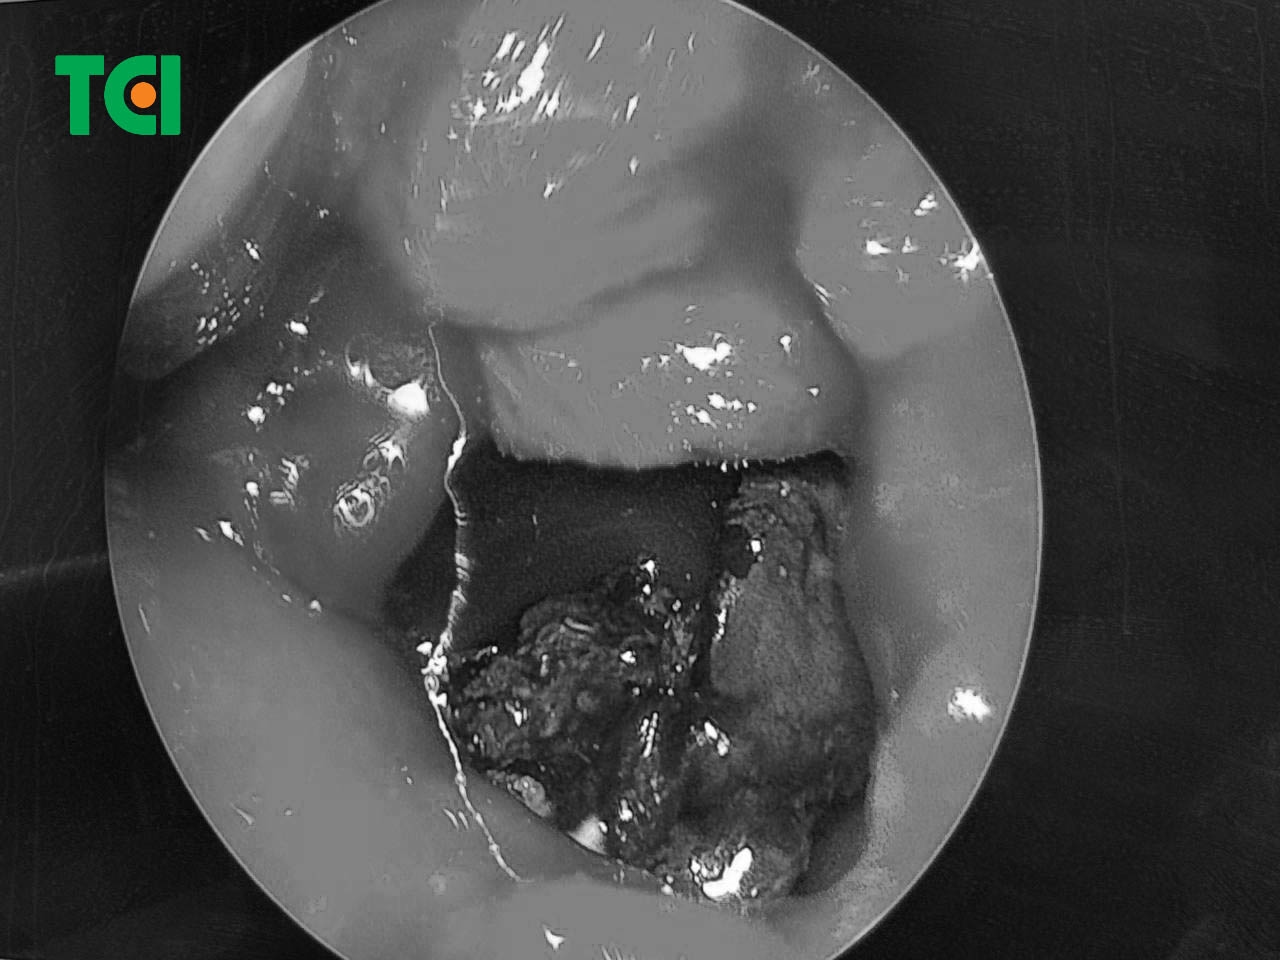

Tại đây, bác T được thăm khám trực tiếp bởi Thầy thuốc ưu tú, Bác sĩ Dương Văn Tiến – Trưởng phòng khám Tai mũi họng TCI, một chuyên gia đầu ngành với hàng chục năm kinh nghiệm. Sau khi thăm khám lâm sàng và thực hiện các chỉ định cận lâm sàng cần thiết như nội soi tai mũi họng và chụp cắt lớp vi tính (CT-scan), bác sĩ đã tìm ra nguyên nhân chính xác gây nên tình trạng của bác.

Bác sĩ Tiến chẩn đoán bác T bị viêm xoang do nấm. Đây là một bệnh lý không hiếm gặp nhưng nếu không được phát hiện và điều trị kịp thời, khối nấm trong xoang có thể phát triển, gây chèn ép, phá hủy các cấu trúc lân cận, dẫn đến nhiều biến chứng nguy hiểm như viêm dây thần kinh thị giác, áp xe não, viêm màng não… Để giải quyết triệt để tình trạng này, phương pháp tối ưu nhất được bác sĩ Tiến đưa ra là phẫu thuật.

Chính xác và triệt để: Ống nội soi với camera siêu nhỏ được đưa vào mũi, giúp bác sĩ quan sát rõ nét toàn bộ cấu trúc bên trong, từ đó loại bỏ hoàn toàn khối nấm và các ổ viêm một cách chính xác.